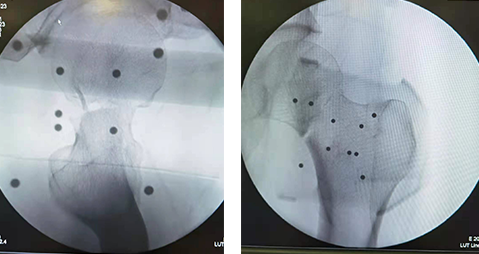

术中规划

术前,“天玑”根据透视影像进行精准定位,术中将虚拟手术计划一一落实到现实,手术路径精确无误。

术中透视正位(左图)术中透视侧位(右图)